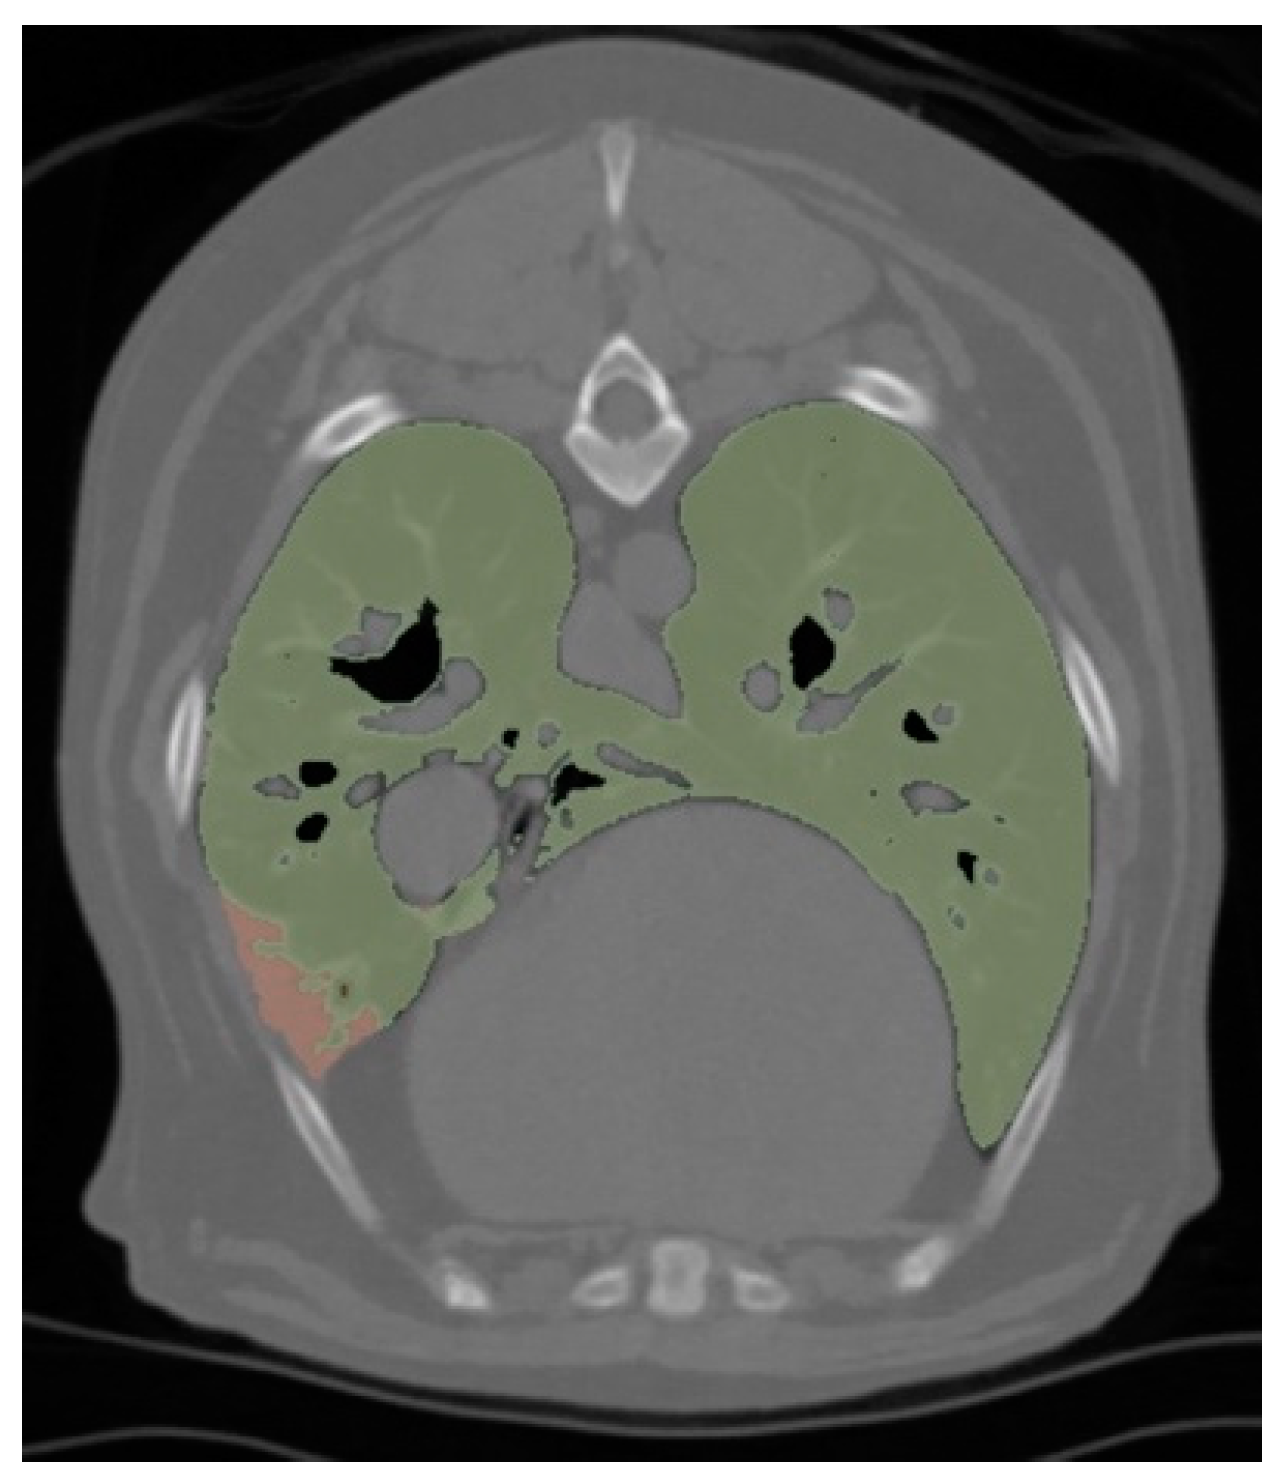

| Respiratory Motion (% of cases) | 19.23 | 7.41 | 0.25 |

| Total Lung Volume (TLV) (cm3) | 1012 (IQR = 698.4–1553) | 951.4 (IQR = 566.4–1274) | 0.51 |

| TLV/Body Weight (cm3 kg−1) | 48.44 (IQR = 35.92–61.76) | 48.04 (IQR = 36.83–60.68) | 0.91 |

| Aerated Lung Volume (ALV) (cm3) | 1100 (SD = 116.5) | 1018 (SD = 106.9) | 0.61 |

| ALV/Body Weight (cm3 kg−1) | 48.08 (IQR = 35.85–61.61) | 47.95 (IQR = 36.82–60.66) | 0.88 |

| Non-Aerated Lung Volume (NLV) (cm3) | 3.66 (IQR = 1.11–5.47) | 1.49 (IQR = 0.39–2.60) | 0.02 |

| NLV/Body Weight (cm3 kg−1) | 0.14 (IQR = 0.09–0.22) | 0.10 (IQR = 0.02–0.13) | 0.03 |

| Aeration (%) | 99.68 (IQR = 99.53–99.79) | 99.82 (IQR = 99.68–99.96) | 0.01 |

| Attenuation of Total Lung Volume (HU) | −724.2 (IQR = −750.0–−679.1) | −716.1 (IQR = −760.7–−676.9) | 0.84 |

| Attenuation of Aerated Lung Volume (HU) | −724.9 (IQR = −751.8–−679.8) | −714.3 (IQR = −760.8–−677.2) | 0.87 |

| Number of Lobes with Atelectasis | 2.00 (IQR = 1.00–3.25) | 1.00 (IQR = 1.00–2.00) | 0.16 |